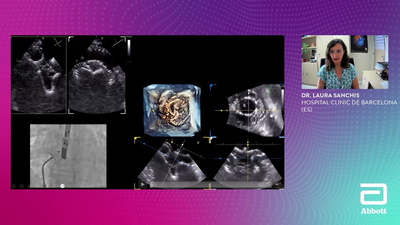

Case Parade | Mitral Focus